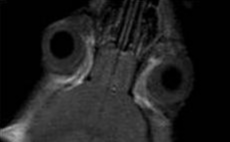

- マウスの涙が眼球を覆っている様子

左:マウスの画像 中央:涙を強調した画像 右:通常の画像

中央の画像では、マウスの眼球のまわりにある涙を観察できます。 -